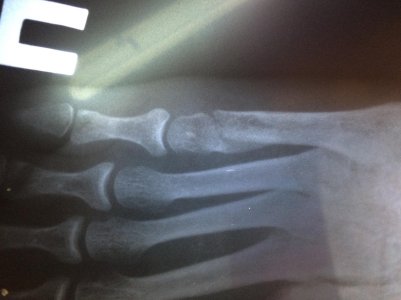

Здравствуйте, мне 19. Рост 150см вес 49, 2 недели назад играла фрисби и повернула ногу, думала ничего серьезного врач приходила сказала связки, спустя 1,5 недели пошла в больницу где мне сделали рентген и написали, что у меня перелом 5-ой плюсневой кости (это написано на польском перевела через переводчик), поставили гипс, сказали через недельку в другую больницу съездить. Сегодня друг забрал мой рентген, посмотрите пожалуйста, ничего серьезного, долго мне придется носить гипс, так как через 5 дней у меня поездка, можно мне ходить? иногда наступаю дома на ногу мне не больно ходить еще. Посмотреть вложение 12228